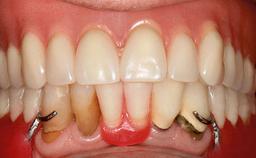

A 74-year-old male patient, a non-smoker, who had been wearing complete dentures for more than 30 years, presented to our clinic complaining about discomfort in connection with his lower denture. The patient suffered from asthma and had a history of cardiac disease and blood pressure disorders. All conditions were medically controlled and stable. The clinical inspection of the oral cavity revealed an ill-fitting complete mandibular denture. The patient expressed the wish for his lower denture to “stop moving when chewing, swallowing, and speaking.” He reported having heard about dental implants and asked whether these could help in “fixing” his lower denture, but also requested non-invasive treatment. The mucosa presented healthy and was free of defects such as pressure sores. An band of keratinized mucosa approximately 2 mm wide was visible. The patient’s mucosal biotype was medium thick to thin.